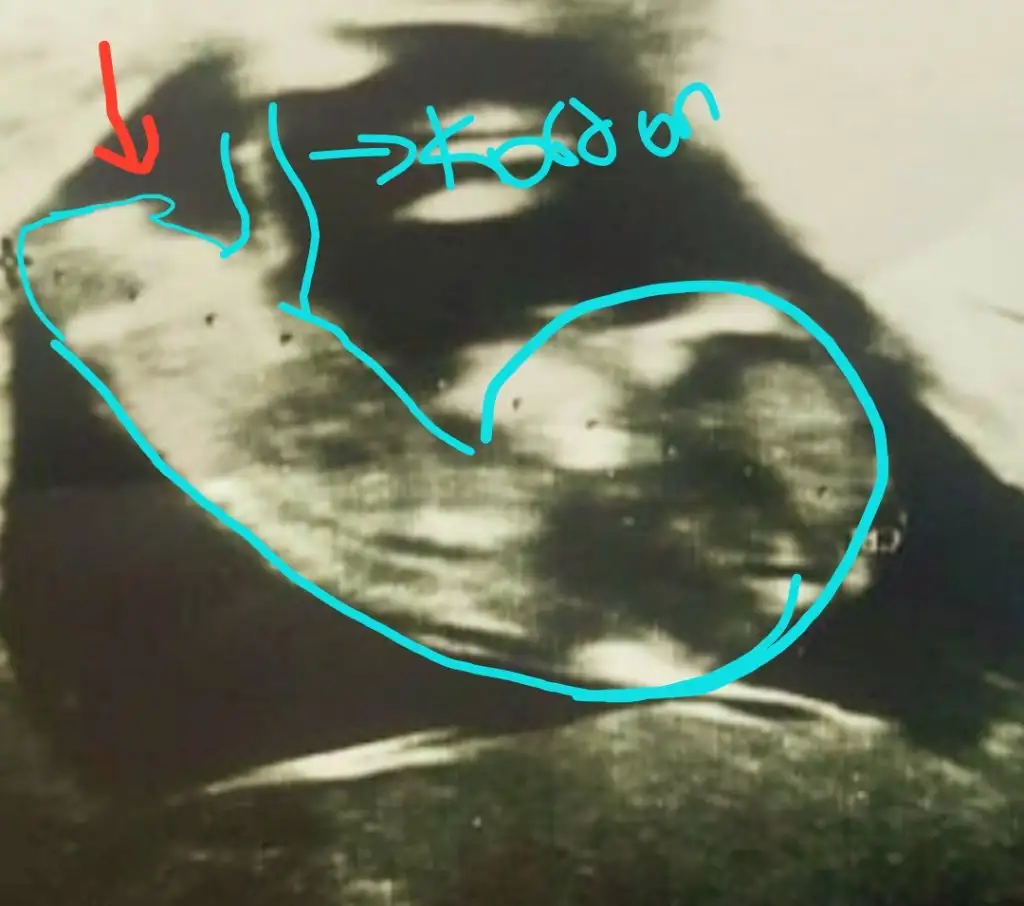

Çok büyük gelmedi bana emin olamadım popoyada paralel değil acısı hafif dik geldi başka USG varsa teyit etmek isterimAttım tekrar bundan baslada yok 12+3

Başka yok sadece bu var tahmini hangiisnden yana kullanmak istersinÇok büyük gelmedi bana emin olamadım popoyada paralel değil acısı hafif dik geldi başka USG varsa teyit etmek isterimEki Görüntüle 2751139

Emin olamadım kiBaşka yok sadece bu var tahmini hangiisnden yana kullanmak istersin

Teşekkür ederim kese konumuna erkek demistin bakalim bu tutacak mı 3 kızım varEmin olamadım kiböyle usgler yanıttı beni %60 erkek derim

Açısı dik değilÖnce kıza benzettim demiştinizbilemiyorum ama bunu dik görünüyor gibi dikkatlice bakarsanız görürsünüz Eki Görüntüle 2751645